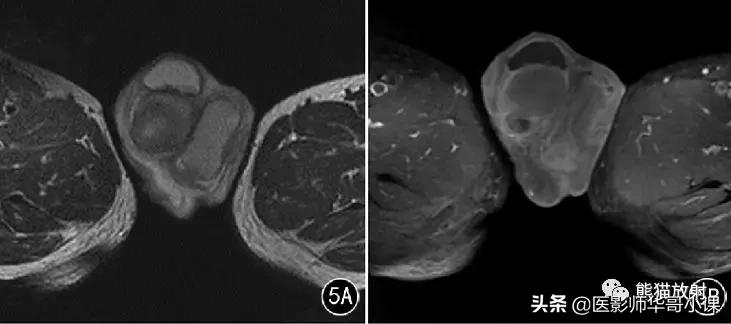

![[精品课件]畸胎瘤及精原细胞瘤(*丸睾**肿瘤及肿瘤样变CT及MR表现)](https://cdn.perryykatherine68.workers.dev/origin/pgc-image/7ead4912973f479e87609a1aa5d86c9d.jpg)

图6 男,66岁, 左侧*丸睾**血肿 。左侧*丸睾**明显肿大,病灶呈T2WI 抑脂(A) 稍高信号,T1WI(B) 高信号,边缘见低信号包膜,包膜内壁多个壁结节突起。